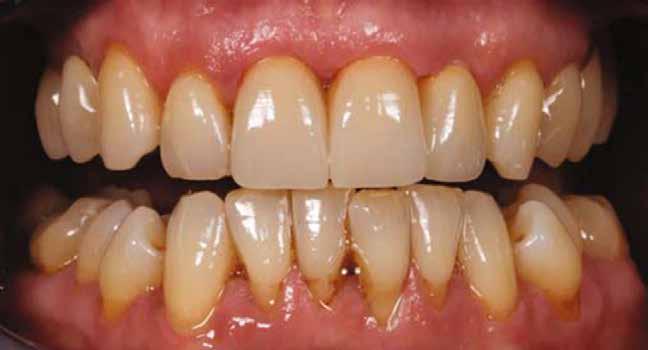

A páciens szájüregi egészségi állapotának a felmérése (1 táblázat).

Kockázati tényezők: túl sok cementet tartalmazó kötőanyag szubmukozálisan.

Implantátum hely: 2.1; Straumann, lágyrész-szint, átmérő: 4,1 mm, hossz: 10 mm, Standard Plus, nyaki rész 1,8 mm. Gyógyszeres kezelés: Amoxicillin 500 mg és Metronidazol 400 mg naponta háromszor 7 napig.

Összefoglalás

A regeneratív kezelést követő 3 hónap után a gyulladás megszűnt. A kezelés előtt a középső periimplantáris nyálkahártyán észlelt, sinus felőli szivárgás megszűnt. A klinikai vizsgálat 12 hónap múlva a periimplantáris szondázási mélység csökkenését mutatta, a periimplantáris gyulladás megszűnésével együtt.

Anyagválasztás:

Geistlich Bio-Oss csontpótló granulátum (méret: 0.25–1 mm), Geistlich Bio-Gide membrán (méret: 13 mm x 25 mm).

1 évvel a kezelés utáni állapot. A kezelés előtti állapot.